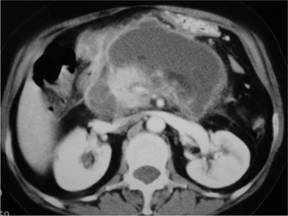

During her admission she developed a fever of 38.5C in association with rigors and was empirically treated with meropenem pending repeated CT imaging which revealed pseudocyst formation (Figure 3). At this point inflammatory markers had increased (CRP 96 mg/L, white cell count 12.7 x109/L) and plans were made to percutaneously drain the pseudocyst. Fluid sent for analysis from the drain came back showing an amylase of 34,613 IU/L, LDH of 2,678 IU/L and an albumin of 0.5 U/L (reference range in serum: 3.5-4.8 U/L); bacterial culture showed this fluid was colonised by Enterococcus and vancomycin was added to the antibiotic regimen. Following drainage the patients fever settled, inflammatory markers decreased and further imaging revealed decreasing size of the pseudocyst. Improvement was such that she was discharged home with a date for elective cholecystectomy.

Figure 3. Axial CT image demonstrating pseudocyst formation. |